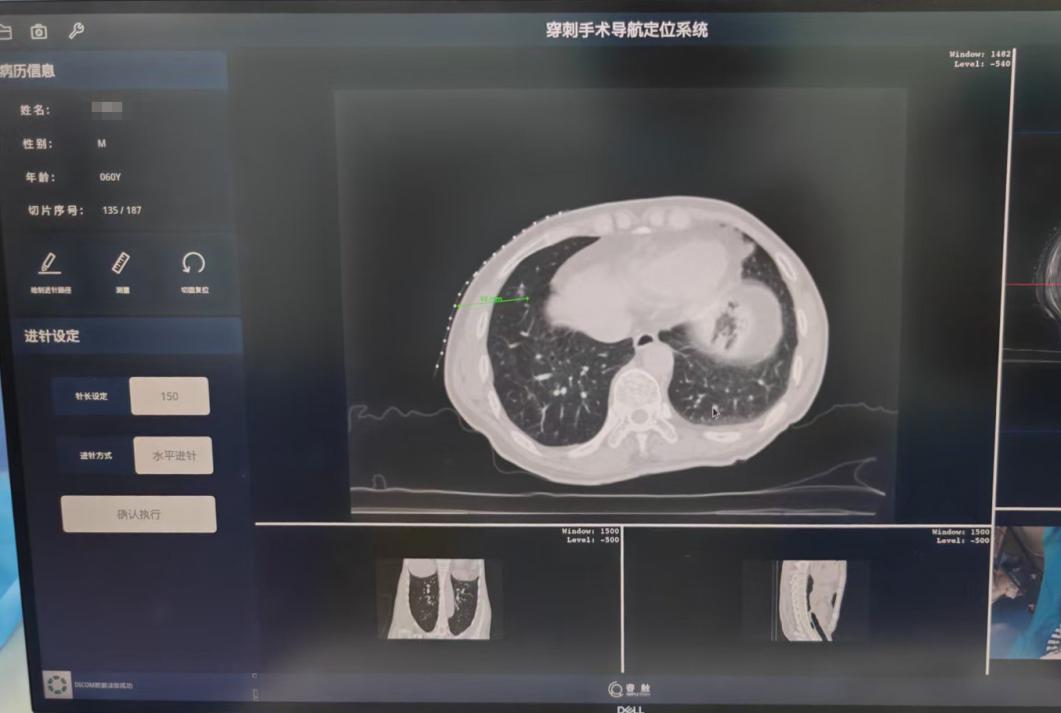

与前者对比,穿刺手术导航机器人具有“CT影像与智能传感一体化”的显著技术优势。团队医生通过CT扫描获取的影像资料,在机器人系统上规划出最优穿刺路径。随后,借助穿刺机器人的导航定位与高精度操作能力,顺利将射频消融针准确穿刺至右肺下叶磨玻璃结节影处。为确保消融针位置完全适宜,团队医生再次进行CT扫描确认,随后分两次开展射频消融治疗。整个操作过程平稳流畅、精准无误,最大限度降低了对周围正常组织的损伤。同时,得益于机器人辅助,显著减少了CT扫描次数,不仅缩短了手术时间,更切实减轻了患者的身心压力与经济负担。治疗结束后,CT复查结果显示,消融区已完全覆盖原病灶,治疗效果达到预期。